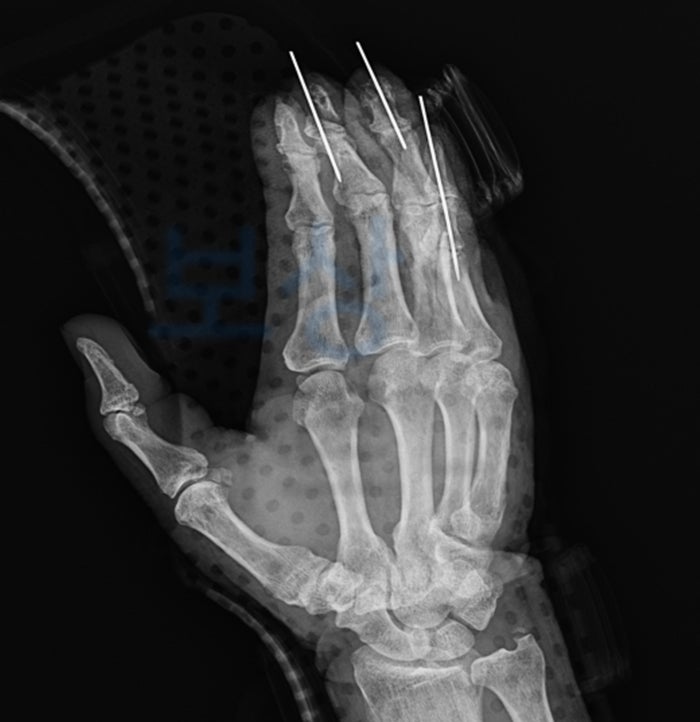

3,4,5 수지 관혈적 정복 및 내고정술

복합조직 이식술

5수지 건봉합술

3,4,5 수지 변연 절제술 및 국소 피판술

골절 부위에는 금속 핀을 삽입하여 고정하였고, 힘줄 봉합 수술과 국소 피판술(옆의 피부를 당겨와 이식)을 시행하였습니다. 깁스 치료가 끝난 후에는 재활 치료도 꾸준히 하셨는데요. 아무래도 예전과 같은 움직임이 돌아오지는 않으셨습니다.